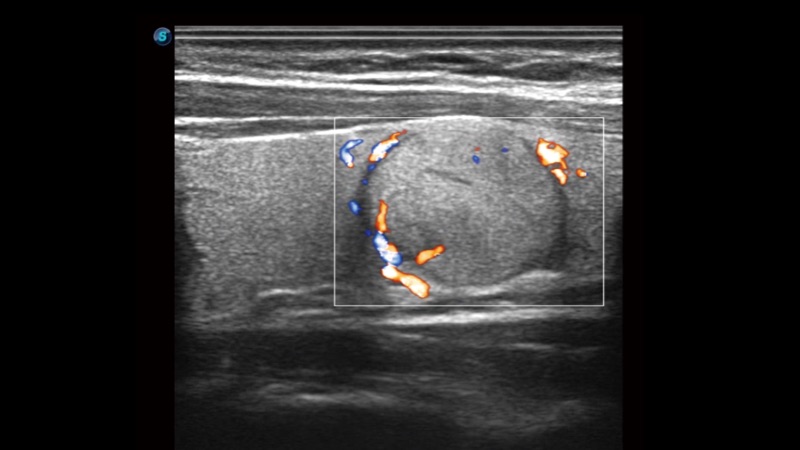

開立醫(yī)療通過不斷的技術(shù)創(chuàng)新,為大眾的生命健康提供持續(xù)關(guān)愛。P12 Plus采用全新一代超聲成像平臺,新平臺旨在將真實(shí)還原組織解剖結(jié)構(gòu)作為首要目標(biāo)。平臺采用全新集成化硬件模塊,搭載新一代芯片,系統(tǒng)性能得到大幅提升,為您的診斷提供了豐富的臨床信息。優(yōu)異的圖像表現(xiàn),豐富的探頭配置,全面的應(yīng)用功能,為您日常診斷提供了可靠的助手。

彩色多普勒超聲診斷系統(tǒng)